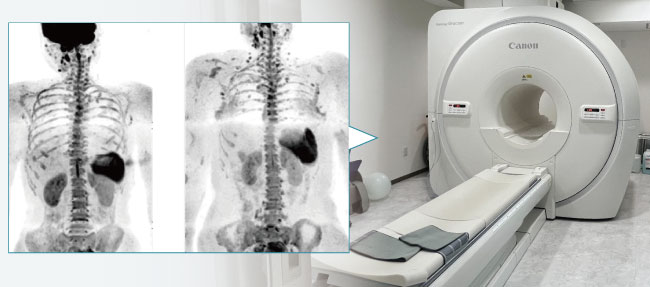

DWIBS(Diffusion-weighted Whole body Imaging with Background body signal:背景抑制広範囲拡散強調画像)は、MRIを用いた最新の全身がん検査です。

これまで全身のがんを調べる検査としてはPET-CTが主流でしたが、DWIBSはPET-CTと比較して検査費用も検査時間も少なく、身体的にも負担が少なく検査を受けることができます。

がん(悪性腫瘍)の組織は通常の組織と比べて細胞と細胞の間が狭い(細胞密度が高い)ことに着目し、細胞と細胞の間の水の動きを画像化することによって病変を検出します。

DWIBSは、体幹部(首の下から骨盤まで)のがん組織の検出が可能です。

予期せぬがんを発見するほか、がんの転移や治療効果の確認などに威力を発揮しています。